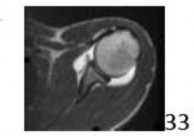

14. # The MRI scan shown in Figure 33 reveals the sequelae of an acute traumatic anteroinferior shoulder dislocation. The image reveals the typical separation of what two commonly injured structures?

1. # Anteroinferior labrum from the bony glenoid

DISCUSSION: The MRI scan reveals the sequelae of an anteroinferior

dislocation, specifically separation of the anteroinferior labrum from the bony glenoid. The separation does not classically occur only at the cartilage-labral junction, but extends to the bony surface of the medial glenoid neck. Separation of the biceps tendon from its origin on the supraglenoid tubercle (SLAP lesion) or separation of the anterior capsule with the proximal humerus (HAGL lesion) may occur but are not the most common sequelae and are not demonstrated in this MRI image. Anteroinferior shoulder dislocations normally do not affect the posterior labral structures. In their landmark study, Rowe and associates noted that this demonstrated lesion was the most common lesion, present in 85% of their series. P R to # 33 is 1.